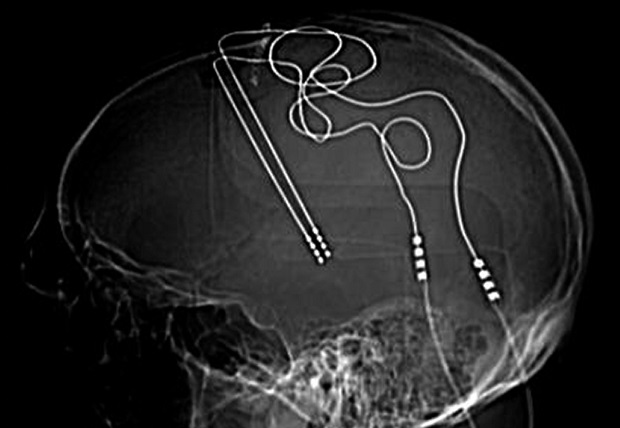

Na prática, o tratamento consiste em uma bateria com condutores especiais implantados na cabeça do paciente, programados para estimular periodicamente de forma controlada determinadas regiões do cérebro. O DBS já foi aprovado nos Estados Unidos para tratar epilepsia, transtorno obsessivo-compulsivo e transtornos do movimento, como a doença de Parkinson, e se espera que a técnica também possa mudar os padrões de atividade anormal nos circuitos neurais que causam os sintomas de depressão.

Recentemente, entretanto, estudos com objetivo de testar a estimulação do SCC como um tratamento para depressão renderam resultados muito abaixo do esperado. A hipótese é que diferenças sutis em onde os cirurgiões colocam os eletrodos são responsáveis pela variação nos resultados dos pacientes. Portanto, o grupo de Helen Mayberg busca uma abordagem de ressonância magnética chamada tractografia para visualizar localizações de feixes de nervos e eletrodos-alvo com mais precisão.

Outras equipes têm uma personalização mais ampla em mente. A psiquiatra Katherine Scangos, da University of California, San Francisco, e colegas estão usando os dados neurais de um indivíduo para decidir qual região-alvo estimular e exatamente quando administrar a estimulação. Antes de inserir os eletrodos DBS, a equipe implanta um segundo conjunto de eletrodos que pode gravar e estimular o tecido em diversas regiões do cérebro. Os cirurgiões já contam com a abordagem, conhecida como eletroencefalografia estereotáxica (sEEG), para identificar a origem das crises antes da cirurgia de epilepsia. Agora, a equipe de Scangos o usou para estimular regiões relacionadas ao humor e selecionar um alvo onde a estimulação alivia os sintomas de forma confiável.